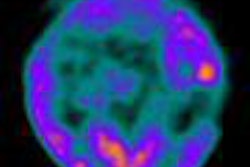

After conventional techniques were unable to find the primary tumor, the team from a U.K. imaging center used PET/CT with FDG to detect primary lesions in a group of patients with squamous cell and undifferentiated cancer neck nodes.

By finding the primary cancer site, the radiologists hoped to guide radiation therapy treatments more accurately, thus sparing healthy tissue. Although PET/CT performed well in general and improved the detection rate of occult cancers, naturally occurring FDG uptake in some normal areas led to false positives. Learn more by clicking here.